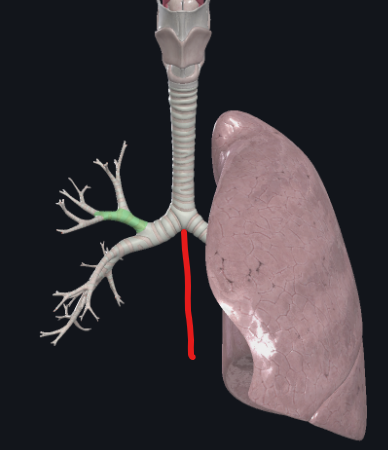

What structure is this?

Diaphragm

What structure is this?

Right main bronchus

What structure is this?

Left main bronchus

What structure is this?

The carina